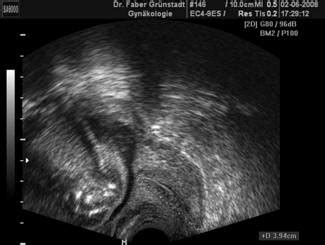

Eine Verkürzung des Gebärmutterhalses (Zervixverkürzung) kann ein frühes Anzeichen für vorzeitige Wehen sein. Die Länge des Gebärmutterhalses wird regelmäßig während der Schwangerschaft kontrolliert, insbesondere wenn Risikofaktoren vorliegen. Messungen wie von 4,9 cm in der 8. SSW, die sich über die Wochen auf 4,4 cm (12. SSW), 3,9 cm (20. SSW) und schließlich 3,2 cm verringert, erfordern eine engmaschige Beobachtung.

Es ist wichtig zu betonen, dass ein Gebärmutterhals von 3,2 cm in der 20. SSW von Ärzten oft noch als nicht dramatisch eingestuft wird, jedoch eine engmaschige Kontrolle und präventive Maßnahmen erfordert. Die Angst, dass sich die Verkürzung fortsetzt, ist verständlich, besonders wenn das Ziel ist, die kritischen Phasen der Schwangerschaft, wie beispielsweise die 33. oder 30. Woche, zu erreichen, ab denen das Kind als deutlich über den Berg gilt.